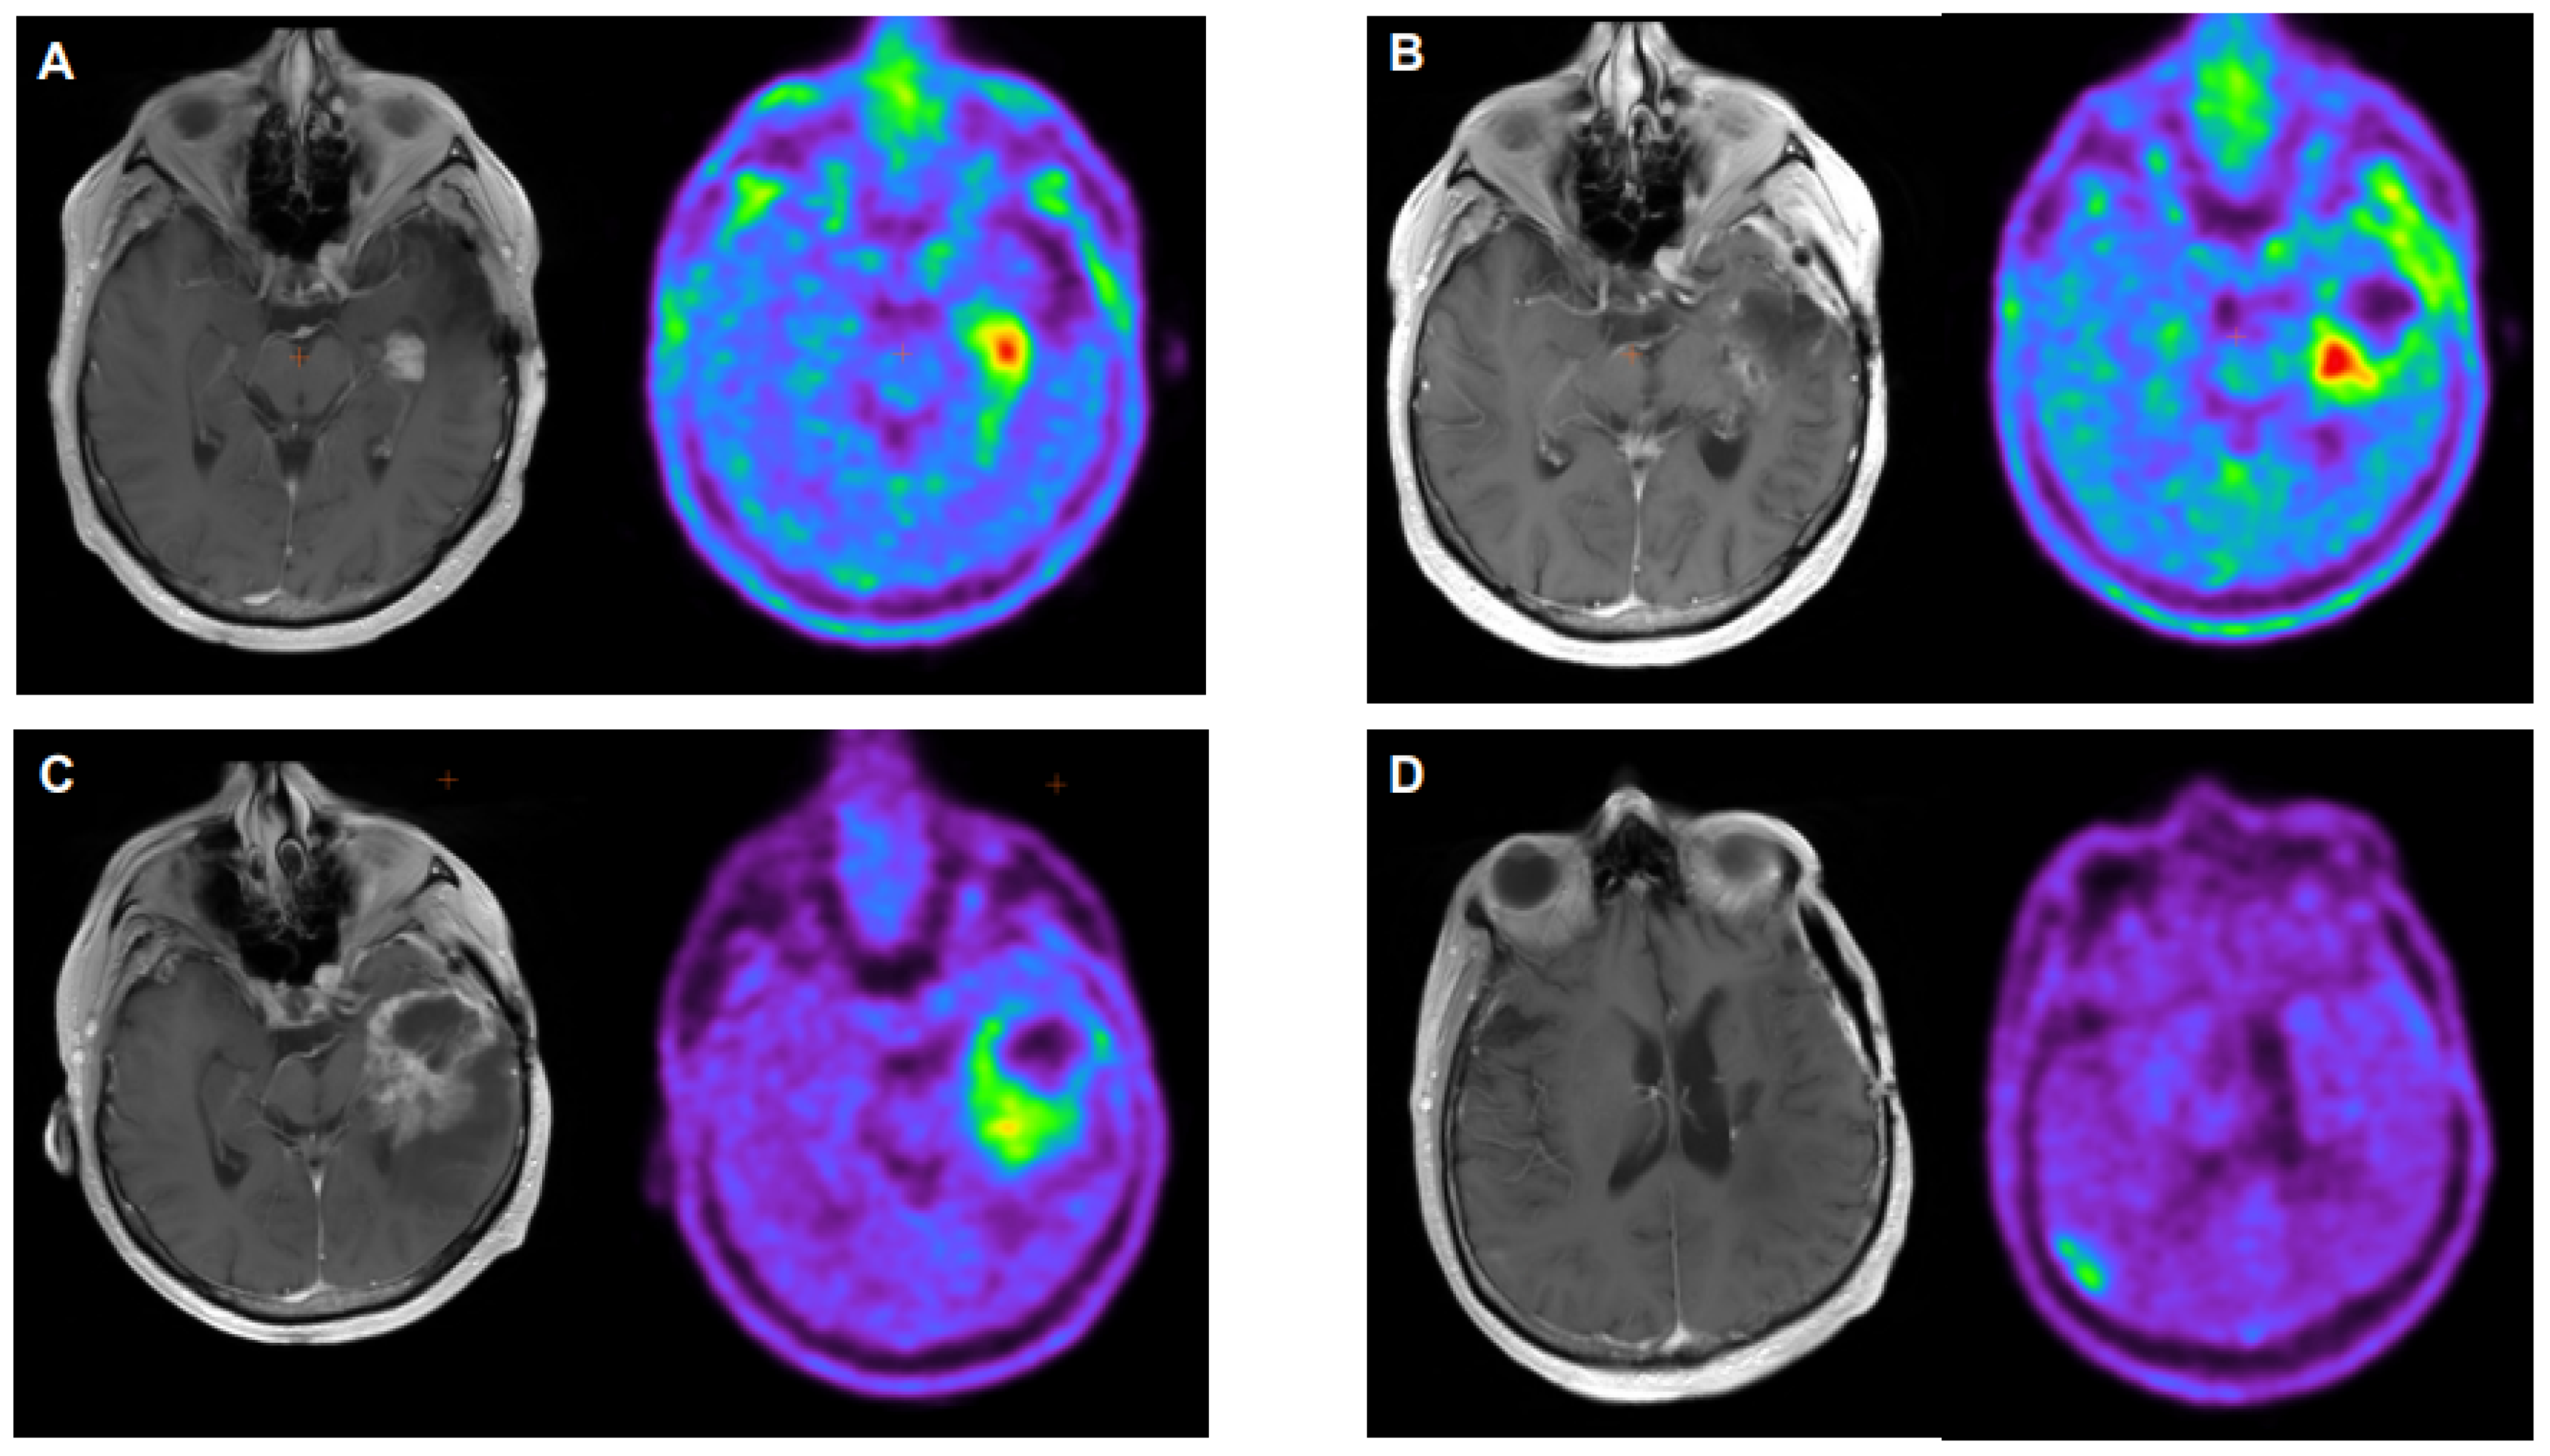

- Maurer, G.D.; Brucker, D.P.; Stoffels, G.; Filipski, K.; Filss, C.P.; Mottaghy, F.M.; Galldiks, N.; Steinbach, J.P.; Hattingen, E.; Langen, K.J. 18F-FET PET Imaging in Differentiating Glioma Progression from Treatment-Related Changes: A Single-Center Experience. J. Nucl. Med. 2020, 61, 505–511. [Google Scholar] [CrossRef] [PubMed]

- Müller, M.; Winz, O.; Gutsche, R.; Leijenaar, R.T.H.; Kocher, M.; Lerche, C.; Filss, C.P.; Stoffels, F.; Steidl, E.; Hattingen, E.; et al. Static FET PET radiomics for the differentiation of treatment-related changes from glioma progression. J. Neurooncol. 2022, 159, 519–529. [Google Scholar] [CrossRef] [PubMed]